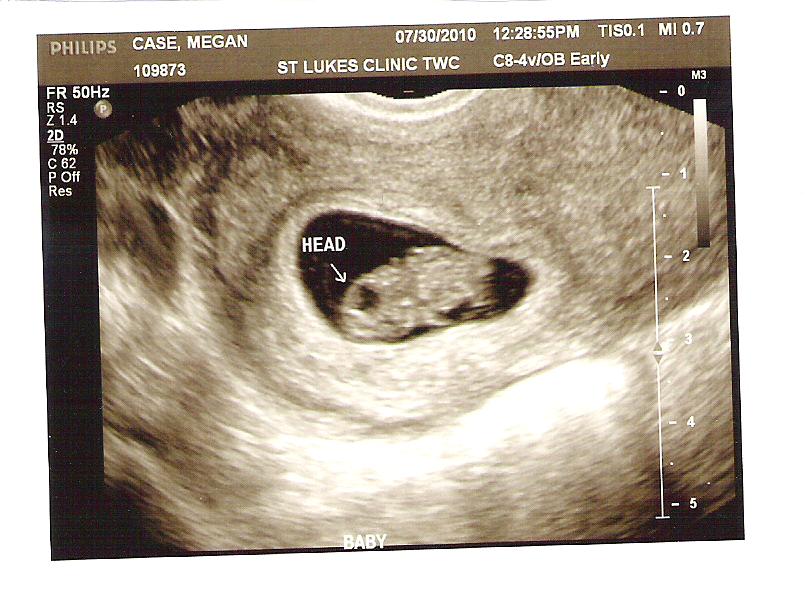

We had our second doctor's appointment today. We were hoping to hear a heartbeat, since we hadn't been able to last time (4 weeks ago, at 9 weeks). The doctor tried for about five (long) minutes to find it with the dopler, but couldn't. Sensing we were discouraged, as was he, he sent us over to the ultrasound side of the clinic. We still weren't able to hear a heartbeat, because they don't recommend using an ultrasound to hear the heartbeat, but we got some new pictures, one of which shows off the cutest little face ever. It was a quick appointment after a long wait in the lobby- we found out later that he was late because he was delivering a baby on the other side of the hospital (good enough excuse for me). We have our next appointment on September 24th and hopefully will be able to tell the gender at our October appointment- and yes, we WILL find out!!!Thursday, August 26, 2010

As of now, we are just under 13 weeks. We are due March 6th, 2011, but I'm hoping to pop perhaps in February. If we do deliver in March, I'm hoping for March 5th, my Grandma Rosie's birthday. We go tomorrow (Friday) for our second doctor's appointment and we're hoping to hear a heart beat- we saw it on the monitor at our first appointment, but we didn't get to hear it. Specifically, we're hoping for a heartbeat of less that 130- a possible factor for having a boy!! I've not experienced much morning sickness, a second characteristic of having a boy...so we'll see.